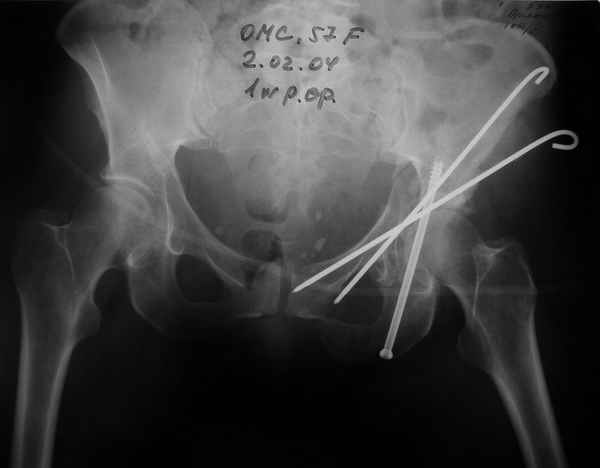

Anatoly F Lazarev 03 Сентябрь 2004, 22:18

Женя! Класный перелом. Отлично репонируется изнутри таза, но лучше фиксированть сзади. Классический перелом для двустороннего доступа.

Однако есть альтернатива. Репозиция из подвздошного доступа тазовыми щипцами с разнодлинными браншами или тазовым пистолетом, а фиксация задней колонны через седалищный бугор или тазрвыми винтами 4,5 или каннюлированными 6,5 или 7,3. По-моему я посылал на ортофорум такой снимок, когда жаловался на ишемический неврит седалищного нерва через сутки после операции. Не забудь про шейку бедра - мне кажется будет хорош длинный PFN любой фирмы, какую ты найдешь, а нет так UFN + miss a nail, как это здорово делают мои земляки - Ебурбуки. Пока.

Высылаю пример еще одного случая, остеосинтез пластиной из подвздошного доступа.